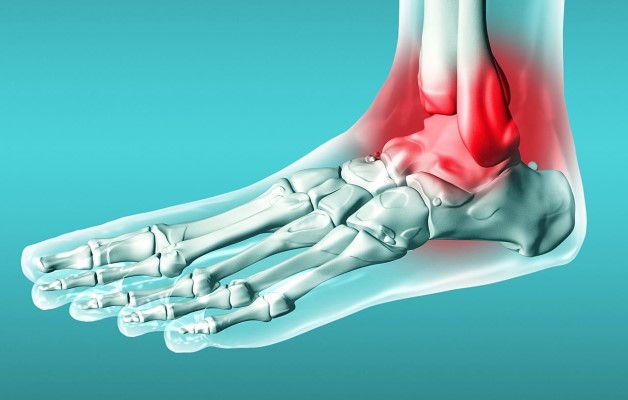

Голеностопный сустав играет важную роль в опорно-двигательной системе человека. Благодаря своей сложной структуре он обладает большой подвижностью, подвергается колоссальным ежедневным нагрузкам, выдерживает вес всего тела. Любая незначительная патология ограничивает амплитуду движения. Артрит голеностопного сустава – заболевание воспалительного характера, которое может развиться в любом возрасте. Оно разрушительно воздействует на суставные и прилегающие ткани, приводит к деформации и, при отсутствии лечения, к инвалидности.

Артрит голеностопного сустава представляет собой воспалительное заболевание, которое может возникать по различным причинам, включая травмы, инфекции и аутоиммунные расстройства. Врачи отмечают, что среди основных признаков артрита можно выделить отечность, покраснение, болезненность и ограничение подвижности сустава. Для точной диагностики важно учитывать анамнез пациента и проводить необходимые исследования, такие как рентгенография или анализы крови.

Признаки голеностопного артрита зависят от причин, клинической картины и степени болезни. Все воспалительные процессы имеют ряд общих симптомов:

- жгучие боли в области сустава;

- отеки – при надавливании на мягкие ткани остаются белые пятна;

- повышение температуры;

- ограничение амплитуды движений;

- покраснение кожного покрова;

- плохое самочувствие и слабость.